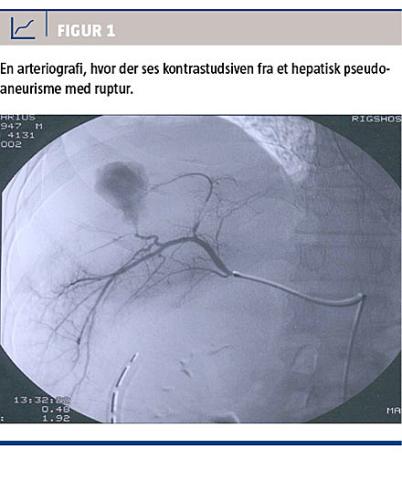

Diagnosen stilles med enten arteriografi, CT med i.v. kontrast (CT-angiografi) eller UL-skanning med Doppler [1]. Arteriografi benyttes sjældent i den initiale diagnostik af HPA, men er til gengæld en del af behandlingen ved TAE. CT-angiografi er ofte førstevalg til diagnosticering af HPA. Med CT-angiografi visualiseres blodkarrene, og den kan optages i både arteriel og venøs fase. Diagnosticering af HPA foretages i den arterielle fase, hvor pseudoaneurismet ses som en kontrastfyldt kavitet ved siden af donorarterien. Ofte ses der et forbindelsesled, selve »halsen«, mellem arterien og pseudoaneurismet.

Er der hul på pseudoaneurismet, vil dette vise sig som kontrastudsiven (ekstravasation) i det omkringliggende væv [1, 18] (Figur 1). UL-skanning med Doppler-flow kan også anvendes i diagnostikken af HPA [3, 18]. Her eftersøger man en turbulent blodstrøm, et såkaldt »yin-yang-tegn«, der viser sig som et rødt/blåt farvemiks langs et blodkar med ensrettet blodgennemstrømning. UL-skanning kan også suppleres med i.v. kontrast (contrast-enhanced ultra sound (CEUS)), men dette er endnu ikke vanlig praksis i Danmark. Flere internationale undersøgelser viser

Taksigelse: Susanne Frevert takkes for Figur 1.